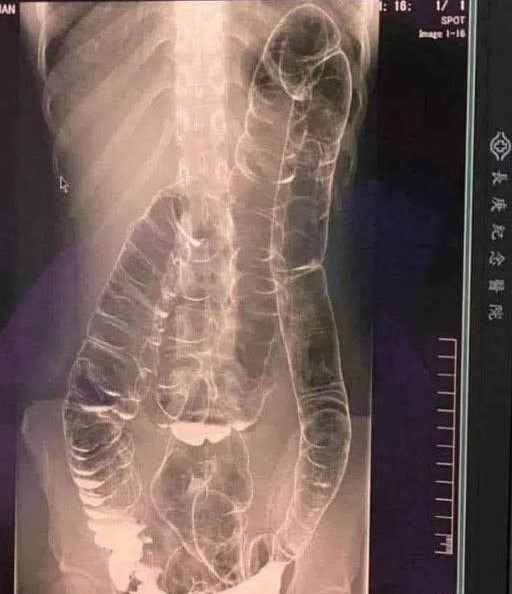

When waste accumulates in the colon due to an inefficient digestive system, it causes severe discomfort and bloating. Over time, the colon expands beyond its normal size, struggling to contain the excessive buildup of feces. In this case, medical imaging revealed a severely distended colon that had enlarged so much it reached up toward the chest, dangerously close to the heart. The stretching had nearly erased the colon’s natural folds and wrinkles, essential for its proper function. Left untreated, this condition could have led to life-threatening complications.